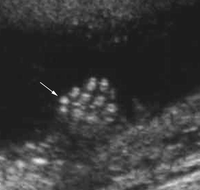

חלל הבטן והחזה: נקודה אקוגנית בלב (אקוגני אומר בוהק באולטרהסאונד), מעי אקוגני, הרחבת אגני כליה, שתי כלי דם בחבל הטבור (נצפה סביב השלפוחית)

בתמונה הבאה מודגם מוקד אקוגני בלב העובר